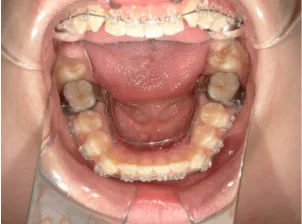

治療中③中1:非抜歯治療の診断で、上顎に歯の生えるスペースをつくるため上顎左右6をプレートで遠心移動し、隙間ができた時点

マルチブラケット法へ移行します

治療中④中1:治療中 マルチブラケット法へ移行